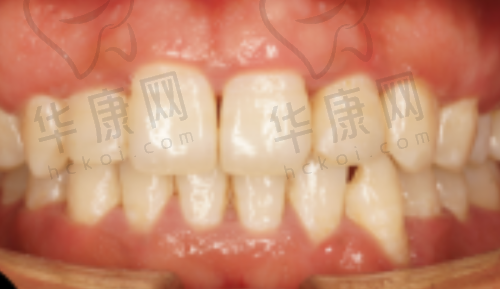

李先生是一位商务人士,由于长期吸烟和喝咖啡,牙齿变得又黄又黑,这让他在商务交往中非常不自信。他来到洛阳拜尔九龙口腔医院,医生为他推荐了树脂贴面项目。经过详细的检查和沟通,医生为李先生制定了个性化的治疗方案。在治疗过程中,李先生没有感到明显的疼痛和不适。治疗结束后,李先生的牙齿变得洁白整齐,他的自信心也大大提升。现在,李先生在商务场合中更加从容自信,对自己的牙齿非常满意。

张女士是一位爱美的女士,她的牙齿存在一些小缝隙和轻微的不整齐,影响了她的笑容美观。她选择了洛阳拜尔九龙口腔医院的树脂贴面治疗。医生根据张女士的面部特征和个人喜好,精心设计了贴面的形状和颜色。治疗后,张女士的牙齿变得更加理想,笑容更加灿烂。她逢人就推荐洛阳拜尔九龙口腔医院的树脂贴面项目。

在网络上,也有特别多患者分享了自己在该医院进行树脂贴面治疗的经历。他们上传了治疗前后的对比照片,让更多人直观地看到了树脂贴面的神奇成效。这些真实的实例和好评,进一步提升了医院的口碑和有名度。